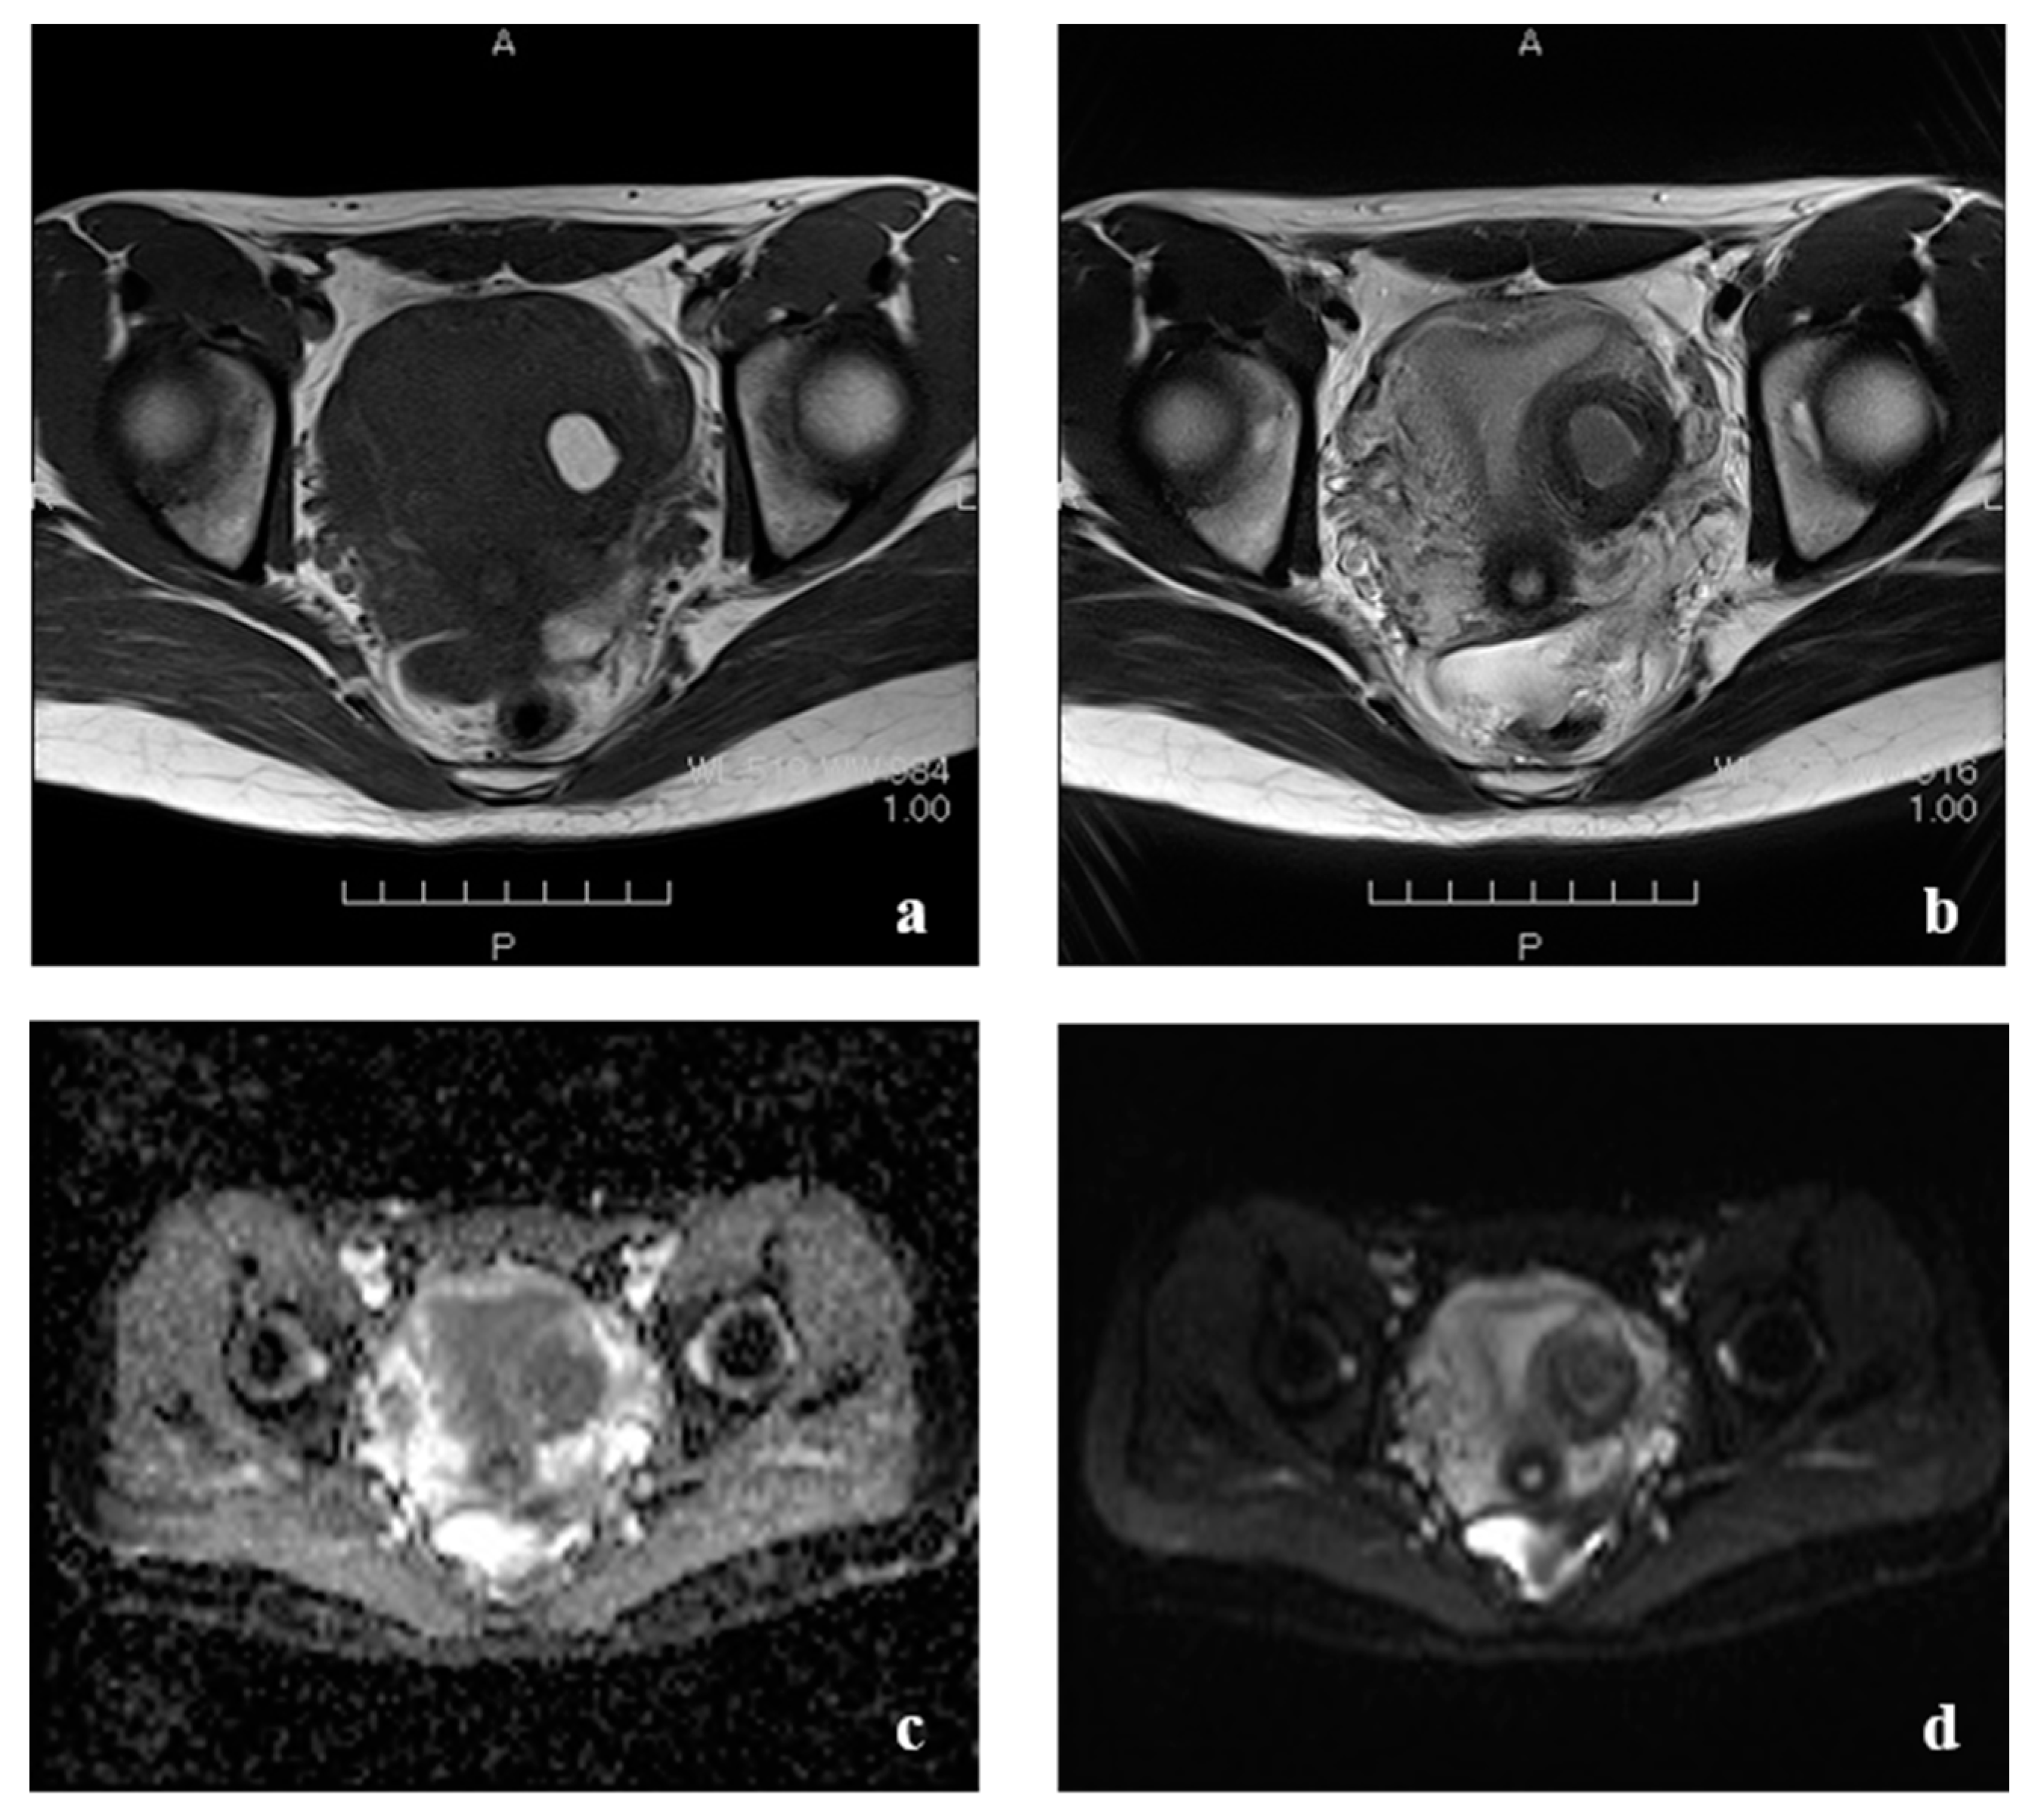

2. Case Presentation

| This case | 22 | 0 | 0 | 15 | 36 | L | 51.9 | None | CT, MRI: None | Laparoscopy | 3 cm, lateral, left side | Harmonic Scalpel, scissors forceps | 2 layers using 0 PDS | 14 | 69 | few | 2 | Present study |